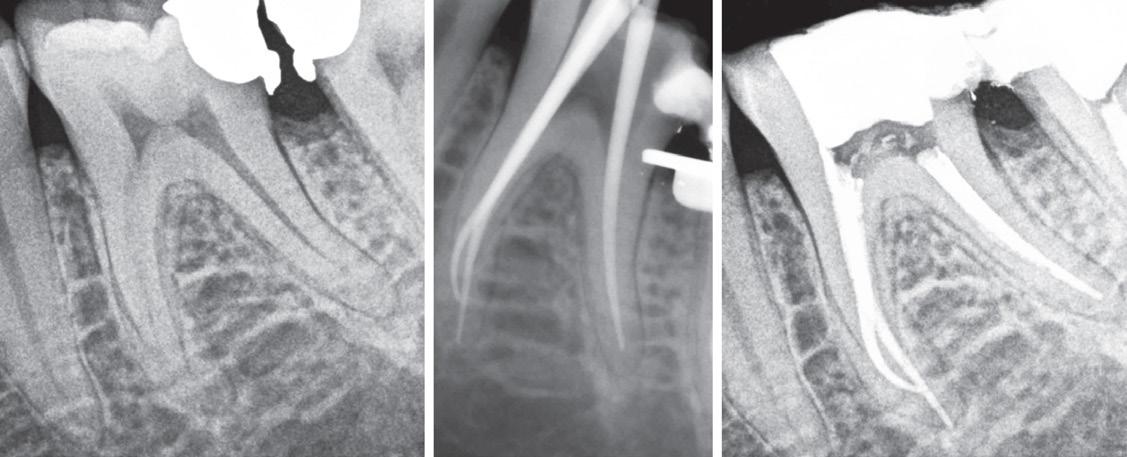

Remarkably, the patient’s chief concern was the gingival recession on the left maxillary lateral, not the mesial caries. (Fig. 8) Fortunately, the patient’s oral hygiene was relatively good, and restoring the MLB decay was

straightforward (BeautiBond (Fig. 7) and Beautifil Flow Plus X, both from Shofu USA, San Marcos CA). The steps for the esthetic rectification of the buccal recession are:

1. Gently micro-abrade the receded area and the apical enamel to remove food debris and plaque. The nozzle of the abrader should be angled incisally to prevent gingival irritation and bleeding. Rinse thoroughly and lightly air dry, leaving the surface slightly moist (although the degree of moistness is not critical).

2. Apply BeautiBond, a 7th generation dental adhesive, and leave for 10 seconds. Thoroughly air dry the adhesive (very critical). Light cure with the Fusion 5 Curing Light (Dentlight, Plano TX), offering deep cure of composite resins within 3 seconds with a uniform 4000 mW/cm2 output. (Fig, 7A)

3. Select the appropriate Beautifil II Gingiva shade (Light Pink and Violet for this patient) and apply to the receded area to restore the buccal dimension and contour of the original soft tissue. Light cure. It is important to leave a small (0.25-0.50mm) gap between the apical margin of the restorative and the free gingival margin. (Fig. 9) This space prevents gingival irritation, is easily maintainable by the patient, and is generally not visible even with closeup photographs. (All photography done with the Shofu EyeSpecial camera, (Fig. 10) Shofu USA, San Marcos CA.)